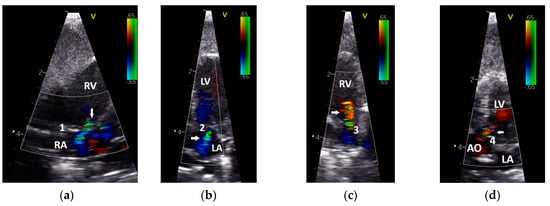

Figure 2.

Insufficiencies of the right (a) and left (b) atrioventricular valve and the pulmonary (c) and aortic valve (d) of Congo grey parrots, visualized by colour flow Doppler echocardiography. Arrow: marked insufficiency jet; RV: right ventricle; LV: left ventricle; RA: right atrium; LA: left atrium; AO: aorta; 1: right atrioventricular valve; 2: left atrioventricular valve; 3: pulmonary valve; 4: aortic valve. The colour scale on the right side of the image is calibrated in m s−1.

Based on their sonographic findings, the GPs were divided into three groups: group 1: cases without sonographic evidence of heart disease (26 cases from 24 GPs); group 2: cases with left heart failure (60 cases from 46 GPs); and group 3: cases with right or with left and right heart failure (63 cases from 53 GPs). The applied classification criteria resulted in clear differences between the groups (Table 2 and Table 3). For example, in group 2, only insufficiencies of the AOV (n = 10) and the AVleft (n = 25) were seen, while in group 3 insufficiencies of the AOV (n = 4), the AVleft (n= 16), the PAV (n = 2), and the AVright (n = 18) could be detected (Table 2; Figure 2). The investigations showed dilatations of the heart ventricles in 34 cases from group 2 and in 63 cases from group 3 (LV: n = 4; RV: n = 27; RV and LV: n = 22; Table 3). In group 3, in some cases with right heart failure, a clear end-diastolic movement of the septum towards the left ventricle (n = 7; Figure 3) could be determined. Furthermore, also in group 3, more clinical signs of congestion in the form of hepatoperitoneal cavity effusion (n = 10) and pericardial effusion (n = 9) could be detected (Table 2; Figure 3).